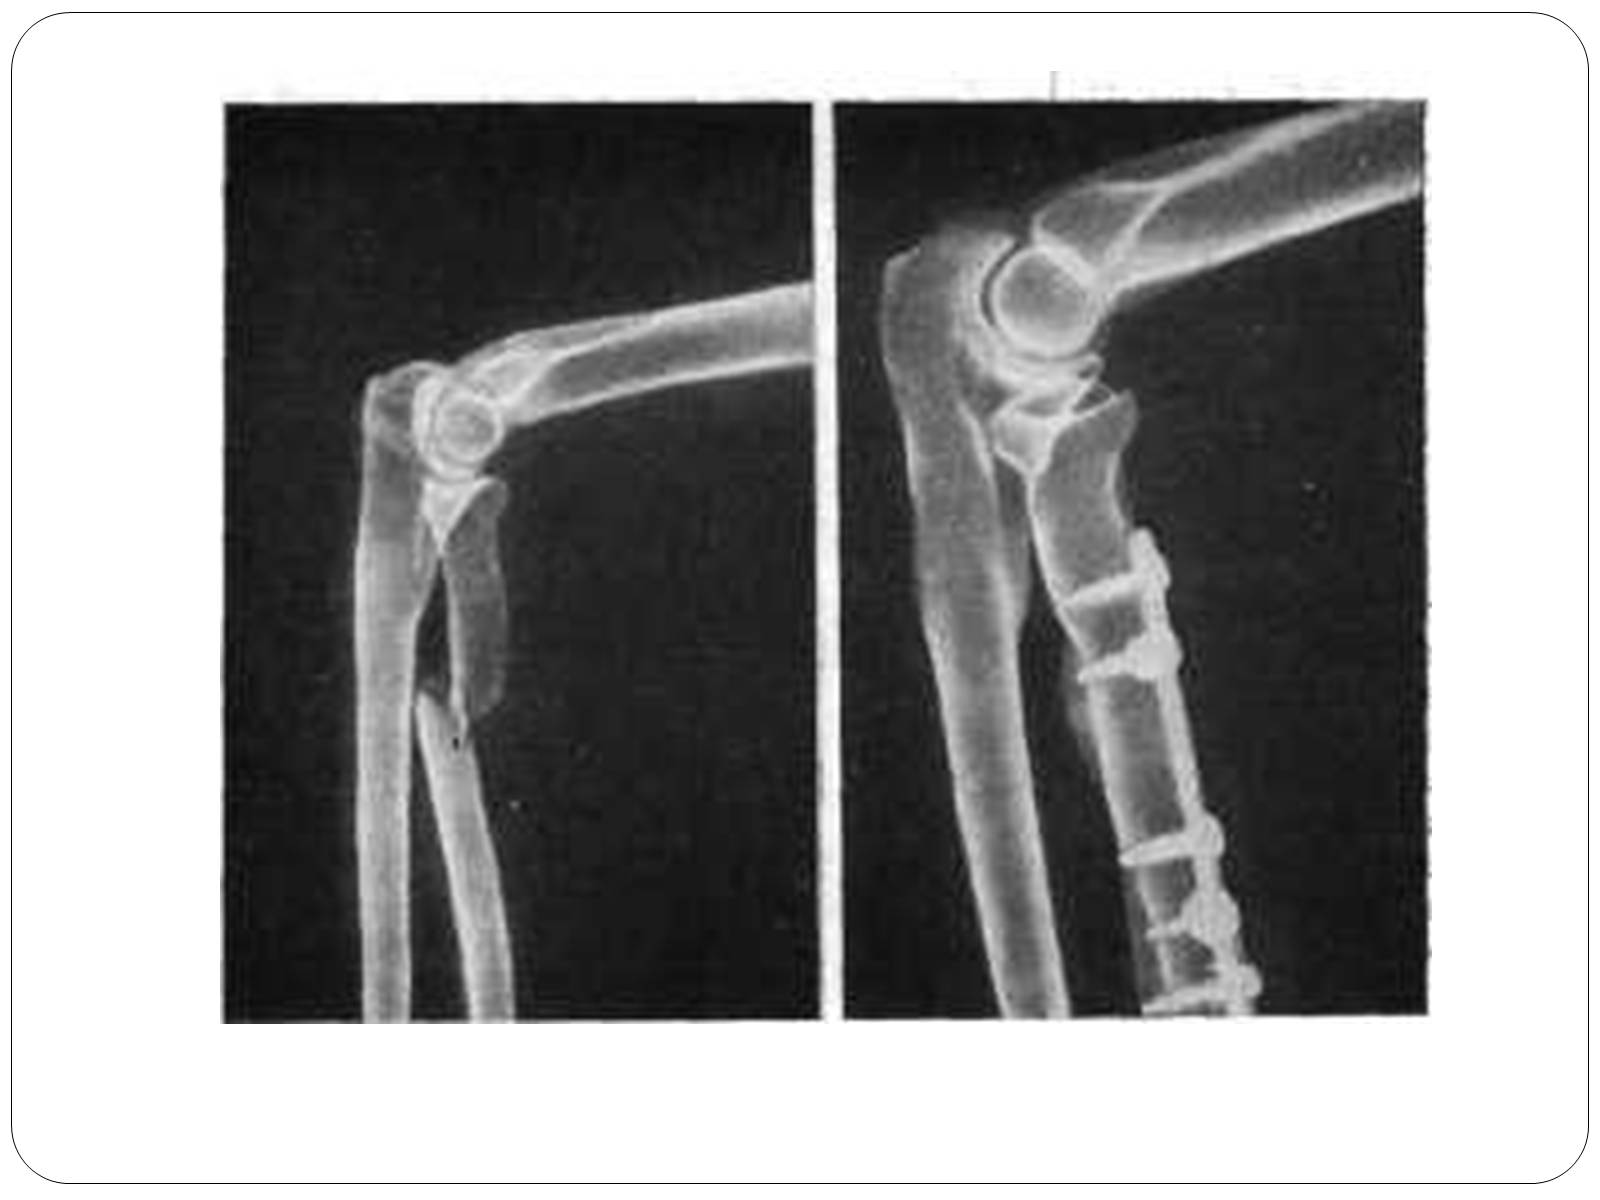

Слайд #24

1) Відкриті

• первинновідкриті

• вторинновідкриті